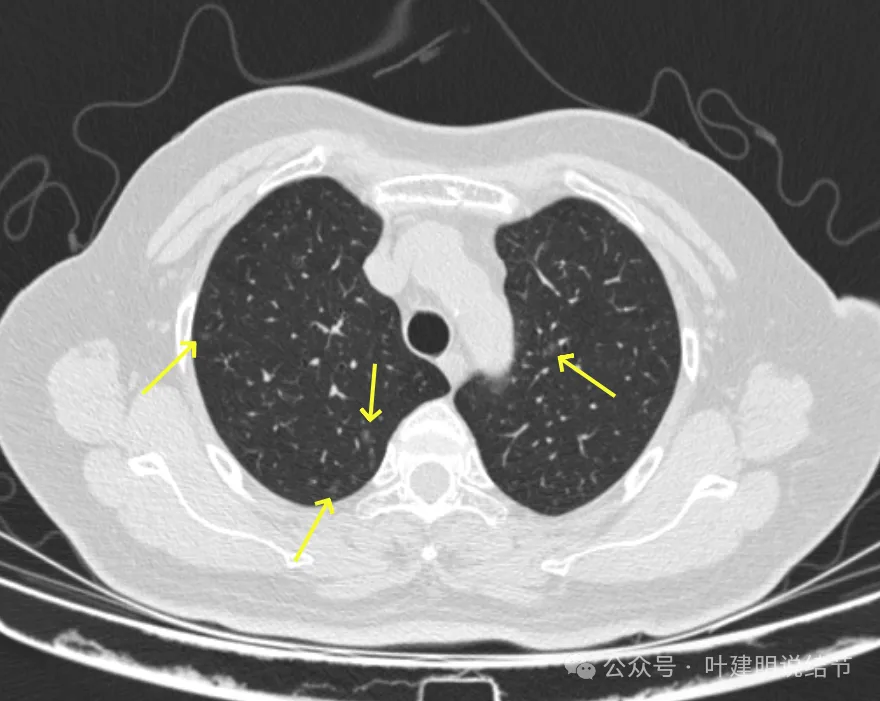

病灶7-9:右肺上叶淡磨玻璃结节,轮廓较清。

病灶10:右侧胸膜下淡磨玻璃结节,轮廓较清。

病灶15-18:右上叶淡磨玻璃结节,轮廓较清,有的界限稍不清。

病灶31:左上叶磨玻璃结节,轮廓与边界清,灶内有偏实性成分,紧贴胸膜,此灶相对较为主要,考虑原位癌或微浸润性腺癌可能性较大。

病灶32:上叶尖后段胸膜下此灶密度较高,有小血管进入,但病灶本身还小,考虑原位癌可能性稍大。